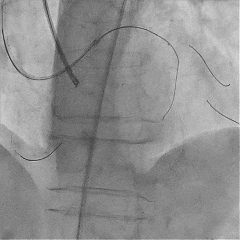

双腔微导管辅助下,导丝在逆向造影指引下成功通过LAD闭塞段,逆向造影显示导丝走行于LAD真腔内

交换工作导丝至LAD远端

预扩球囊依次扩张LAD近中段病变处,造影可见远端血管显影,导丝位于真腔。

于LAD近中段植入Tivoli 2.75*33mm支架一枚,高压球囊后扩张后,血流TIMI3级